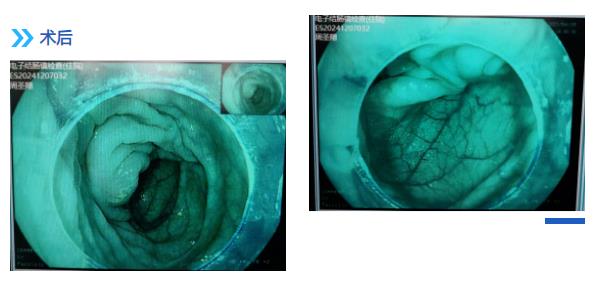

退镜观察见阑尾开口呈半月形,回盲瓣唇型、光滑,通过活检孔道送入一次性成像导管, 后寻腔将一次性成像导管送入阑尾腔,腔内可见多块成形粪石,使用一次性内镜取石网篮粉碎取出多块粪石,应用生理盐水冲洗阑尾开口可见粪石流出,同时可见絮状脓性分泌物流出,后反复观察阑尾腔内,无明显粪石存留,阑尾腔内管壁局灶略粗糙充血发红,近阑尾口处为著。余所见肠腔通畅,肠瓣形态正常,粘膜光滑,无充血水肿, 血管网清晰,未见糜烂、溃疡、息肉、瘢痕及新生物。

手术过程顺利,患者术后恢复良好。